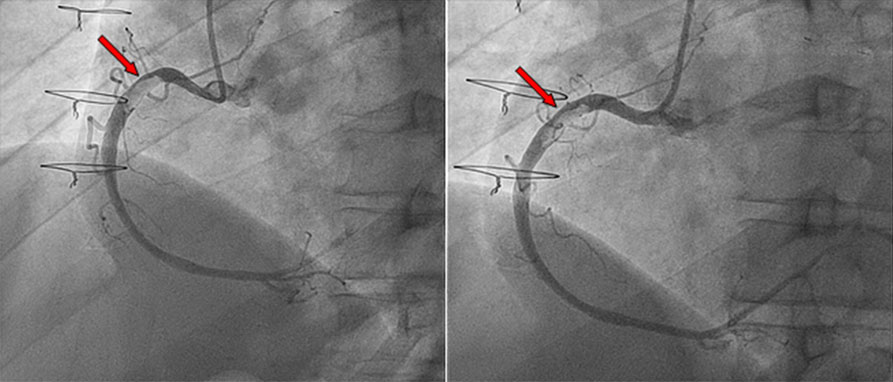

How should I treat residual large right coronary thrombus in a recent-healed #COVID19 patient with #STEMI? View part 1 of this case submitted by a team from 🇮🇹 and share how you would treat! ow.ly/3REk30rFd6w #Cardiotwitter #CardioEd

How should I treat residual large right coronary thrombus in a recent-healed #COVID19 patient with #STEMI?

View part 1 of this case submitted by a team from 🇮🇹 and share how you would treat!

How should I treat residual large right coronary thrombus in a recent-healed #COVID19 patient with #STEMI? View the treatment options retained by the authors as well as the opinion of a different team 😷🩺! pierredeharo Spychaj Jean-Charles Edgar Illescas ow.ly/bwxy30rG3ss

View the treatment options retained by the authors as well as the opinion of a different team 😷🩺! <a href="/deharo_pierre/">pierredeharo</a> <a href="/SpychajC/">Spychaj Jean-Charles</a>  <a href="/IllescasEdgar/">Edgar Illescas</a>

1/ For the fellows and #ACCEarlyCareer! It’s a coronary thrombus! When to consider thrombectomy? What do you do? Let’s walk through this…#Tweetorial #Cardiotwitter #Cardiology #STEMI

1/ For the fellows and #ACCEarlyCareer!

It’s a coronary thrombus! When to consider thrombectomy? What do you do? Let’s walk through this…#Tweetorial

“Thrombus aspiration in coronaries is a class III indication”, a statement often heard in many cath-lab. ROUTINE thrombus aspiration is a class III. It’s mandatory to make decisions case by case. #cathlab #STEMI #thrombusaspiration Giuliano.Iac Dario Prozzo